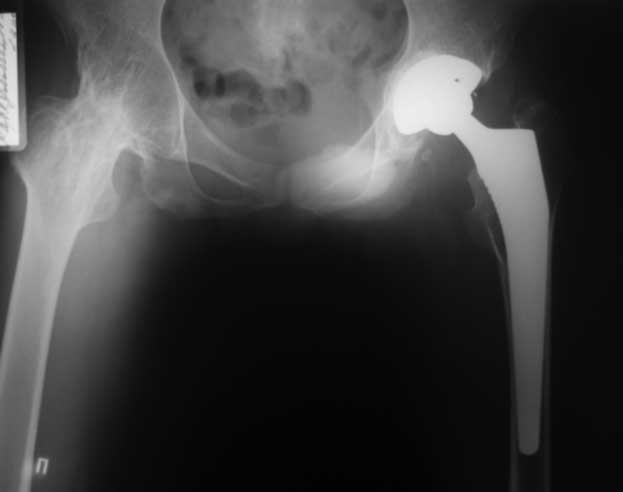

Уважаемые коллеги. пациент, страдает ревматоидным артритом с детства, ранее докладывался...

костный анкилоз т/б суставов. 4 месяца назад THR левого т/б сустава, движения в т/б суставе приличные - с/р 90/5/0, движения в коленном суставе ухудшились - с/р 120/45/0. В настоящее время конечность неопорна из-за сгибательной кнтрактуры в к/с Вопросы о дальнейшей тактике лечения (пациенту 28 лет):1. рассматриваются варианты остеотомий (бедра, б/б кости), насколько это целесообразно, учитывая необходимость артротомии (остеофиты), каков может быть ожидаемый результат? варианты остеотомий (бедро или голень)?2. эндопротезирование к/с: мягкотканный дисбаланс- достаточно будет релиза капсулы и связок или мышцы тоже (учитывая разгибание в т/б после эндопротезирования и натяжение мышц на уровне колена после этого) Чего опасаться и к чему быть готовым?3. другие варианты? ссылки на литературу?собств наблюдения?С уважением Максим Агалаков